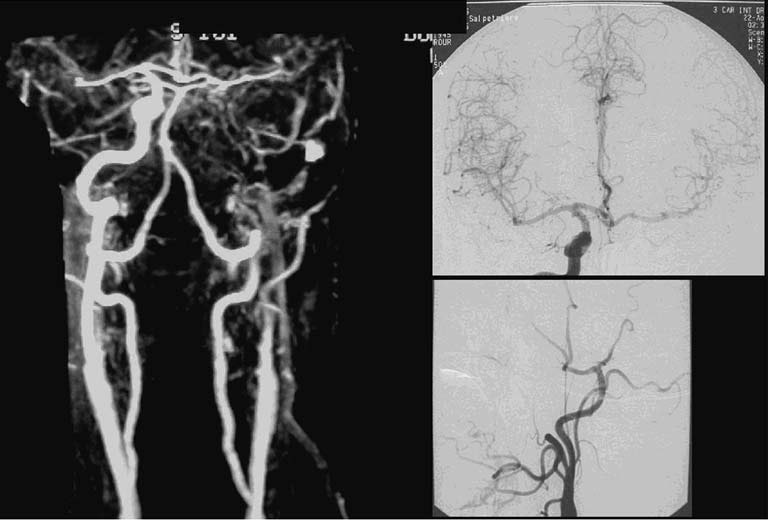

Artériographie de la carotide commune et interne droite de profil (A)... Download Scientific . le suivi par doppler carotidien régulier est essentiel. Restez informé pour prendre les bonnes décisions en cas d'urgence médicale.